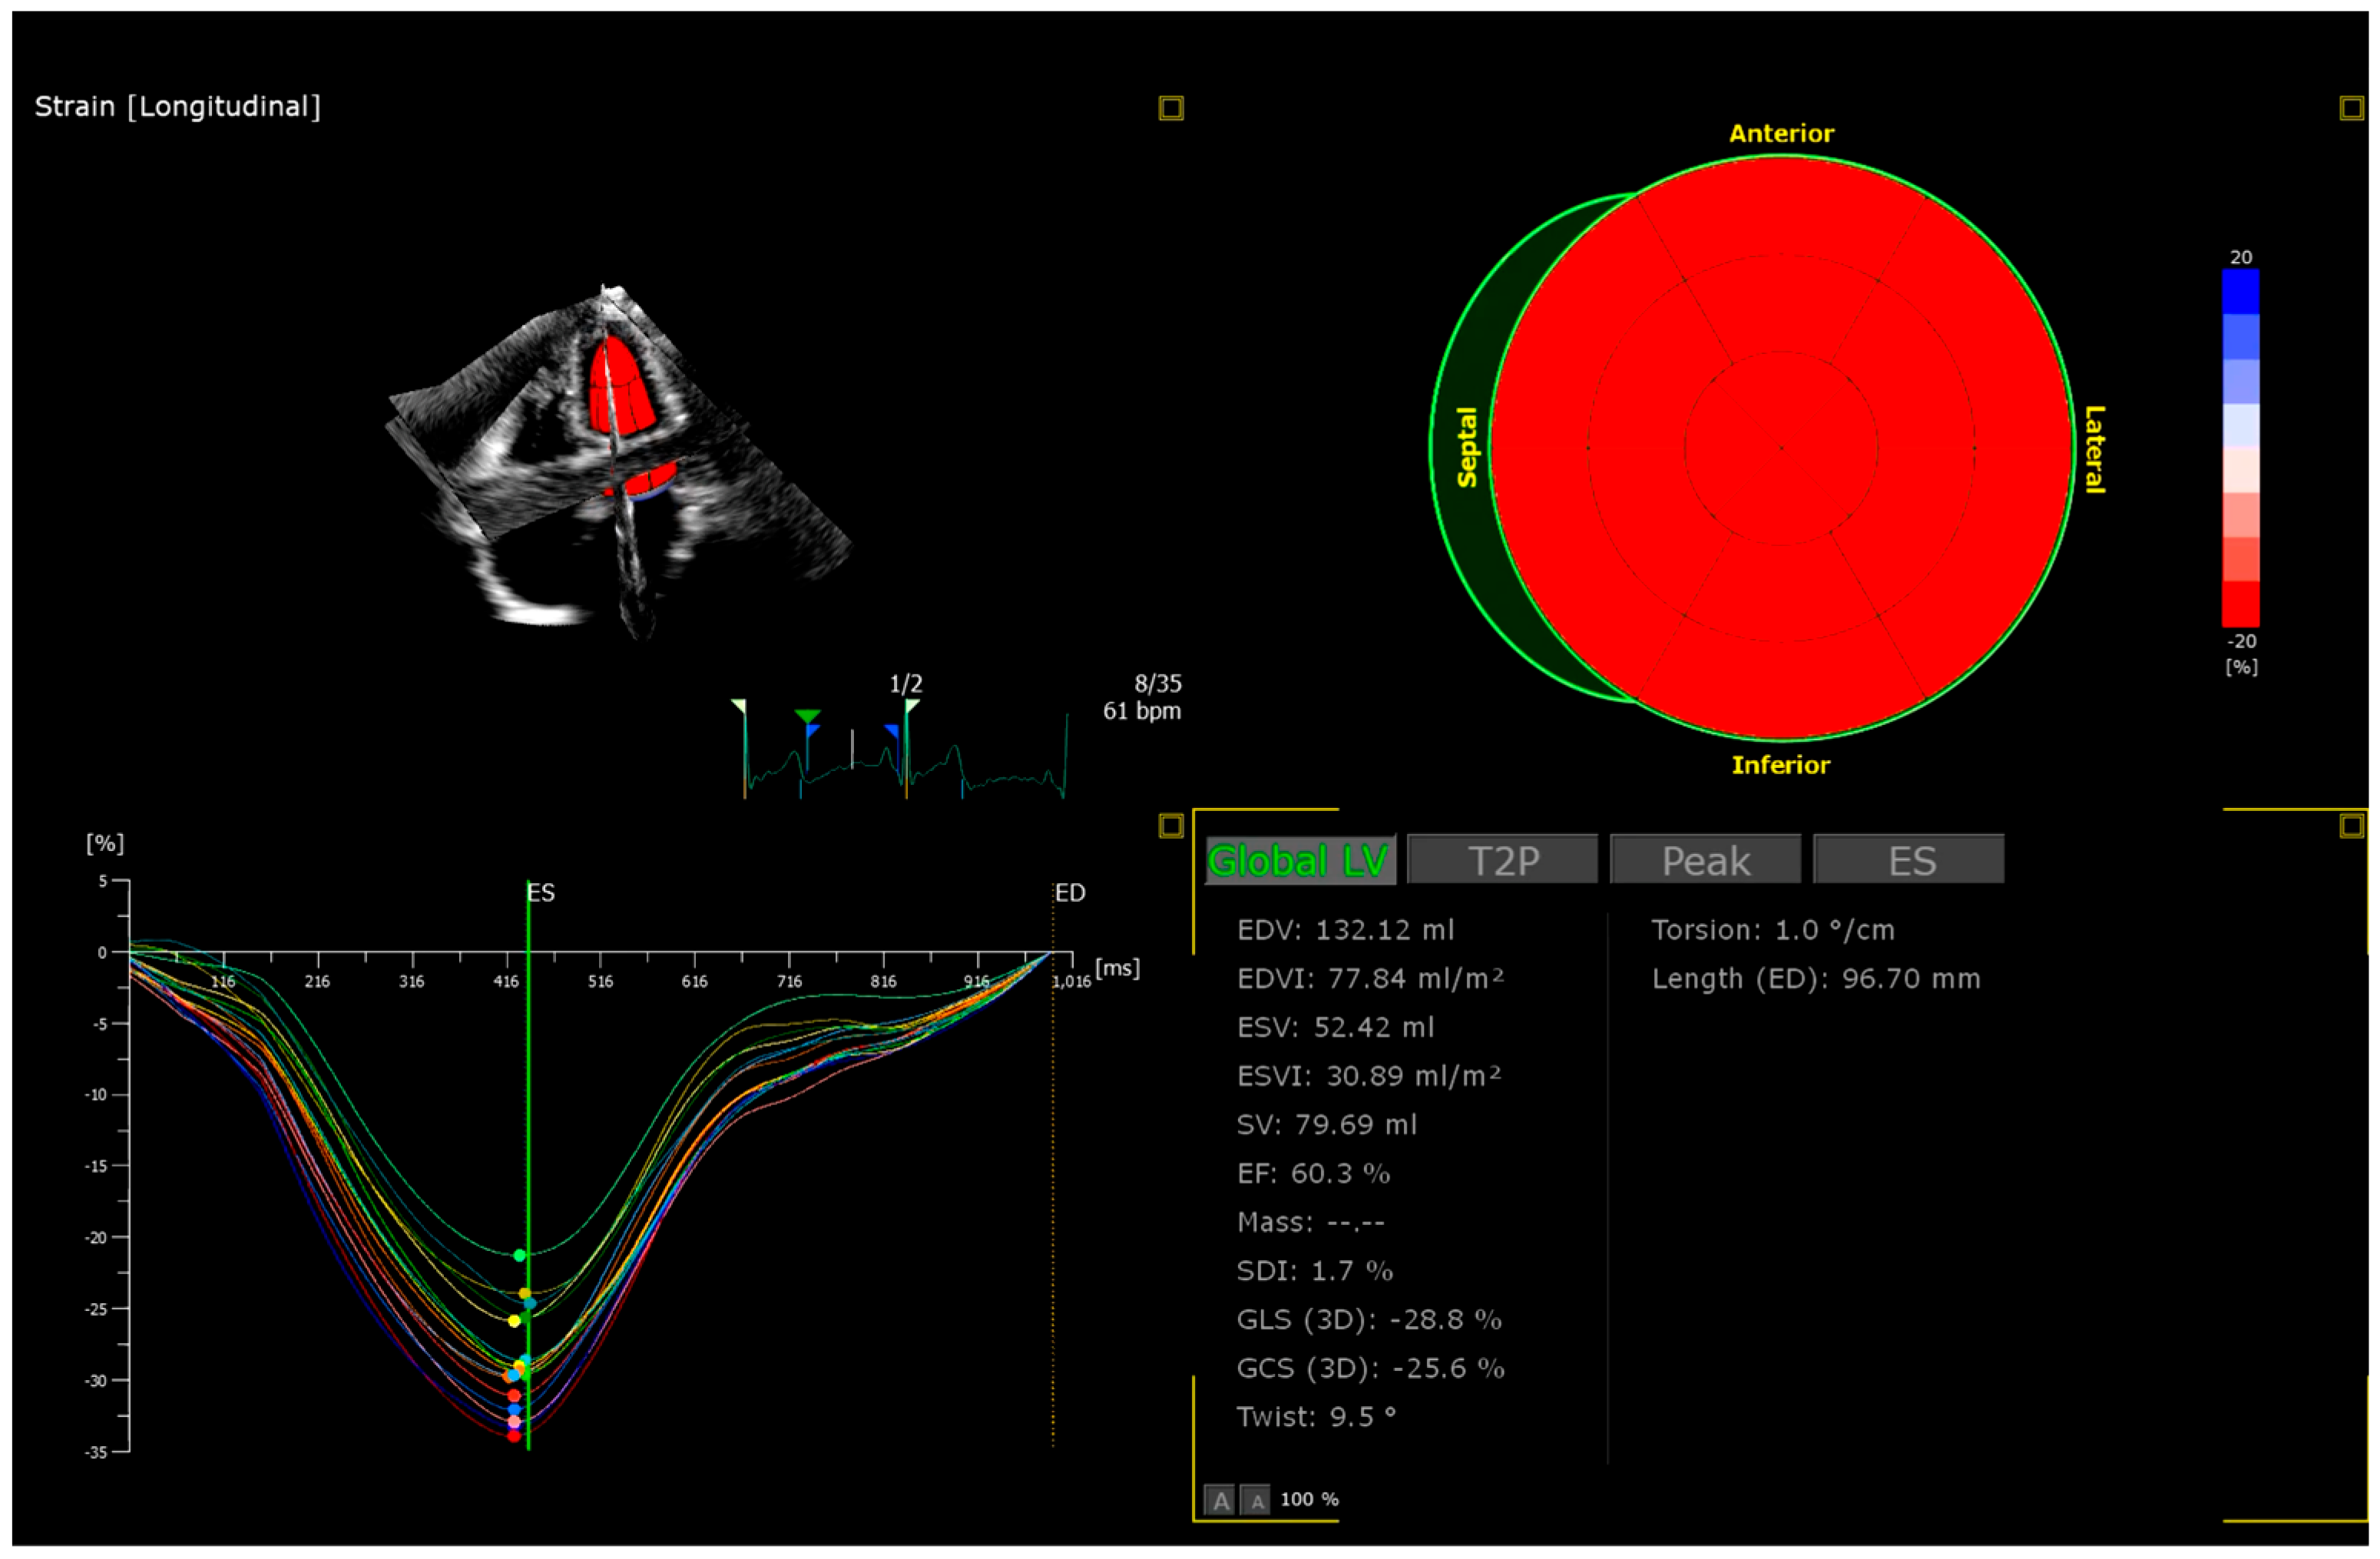

| 3D Echocardiography | |||||

| EDV-3D (mL) | 52.0 ± 23.1 | 55.6 ± 22.8 | 0.55 t | −2.2 (−9.5/5.2) | −0.134 cd |

| EDVI-3D (mL/m2) | 58.8 (52.7; 64.9) | 56.5 (47.3; 64.8) | 0.31 w | 4.5 (−4.6/13.6) | 0.233 wr |

| ESV-3D (mL) | 20.4 ± 8.5 | 25.8 ± 10.5 | 0.13 t | −4.0 (−9.3/1.3) | −0.337 cd |

| ESVI-3D (mL/m2) | 23.2 ± 5.6 | 27.7 ± 7.0 | 0.02 t* | −4.8 (−7.4/−2.3) | −0.883 cd |

| LVEF-3D (%) | 59.7 ± 7.3 | 55.1 ± 3.1 | 0.01 t* | 5.5 (1.8/9.2) | 0.656 cd |

| Length (ED) 3D (mm) | 64.5 ± 8.9 | 66.2 ± 8.3 | 0.23 t | −1.2 (−3.3/0.8) | −0.684 cd |

| LV-GLS-3D (%) | −23.3 ± 5.3 | −20.4 ± 2.8 | 0.03 t* | −2.1 (−4.9/0.7) | −0.756 cd |

| LV-GCS-3D (%) | −26.3 ± 5.9 | −21.9 ± 3.2 | 0.02 t* | −3.8 (−6.8/−0.8) | −0.555 cd |

| LV-GRS-3D (%) | 35.4 ± 20.0 | 35.9 ± 3.6 | 0.45 t | 2.4 (−4.1/8.9) | −0.165 cd |